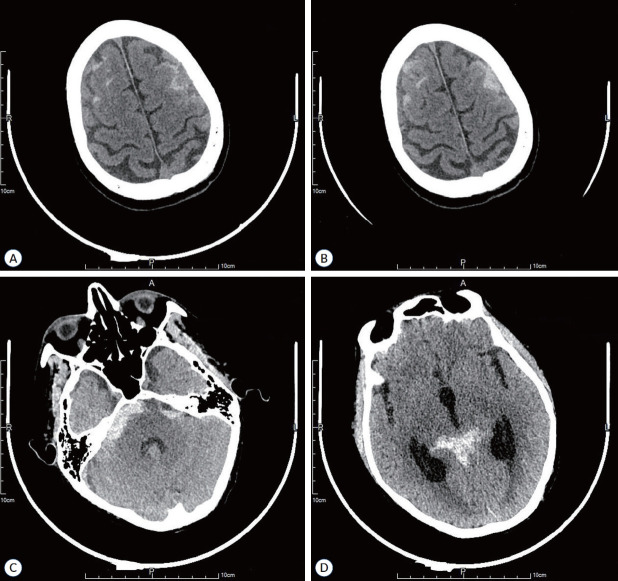

Microscopic polyangiitis (MPA) is a rare autoimmune disorder characterized by small-vessel vasculitis and the presence of anti-neutrophil cytoplasmic antibody (ANCA). Typically, MPA primarily affects the respiratory system, kidneys, and skin, with infrequent involvement of the nervous system, resulting in neuropathy. However, the occurrence of subarachnoid hemorrhage (SAH) in MPA is exceedingly rare, especially when it is accompanied by hemorrhagic events in multiple organs. This case report details the clinical presentation of a 61-yearold male patient diagnosed with MPA who experienced an exceptionally uncommon occurrence of SAH, coupled with extensive bleeding manifestations including epistaxis, skin purpura, and gastrointestinal bleeding. Notably, the patient's symptoms exhibited potential improvement following a treatment regimen consisting of rituximab and glucocorticoids. This case emphasizes the critical importance of promptly recognizing and comprehensively managing rare complications in MPA patients to optimize clinical outcomes.

Abstract Image